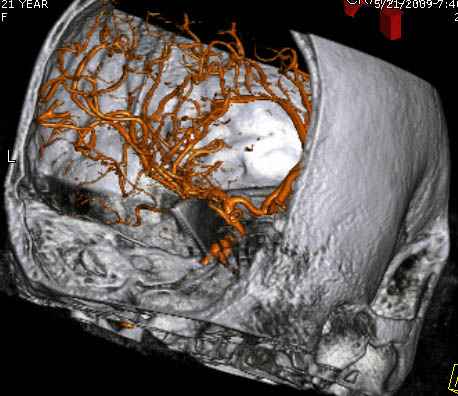

По протоколу сделаны все необходимые исследования: рентген, ангиограмма с 3Д реконструкцией, где обнаружили что все жизненно важные сосуды не задеты, даже некоторые "сидят" изгибаясь на ноже.

Одним махом нож удалить не удалось, пришлось раскачать и потом двумя руками удалили нож. Рана без кровотечения, обработана и зашита.